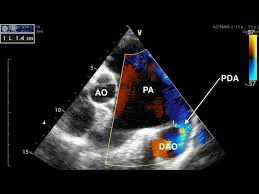

동맥관 개존 (Patent Ductus Arteriosus, PDA)

정의: 출생 후 정상적으로 닫혀야 할 동맥관이 계속 열려있는 상태

심초음파: 동맥관과 단락 혈류 확인